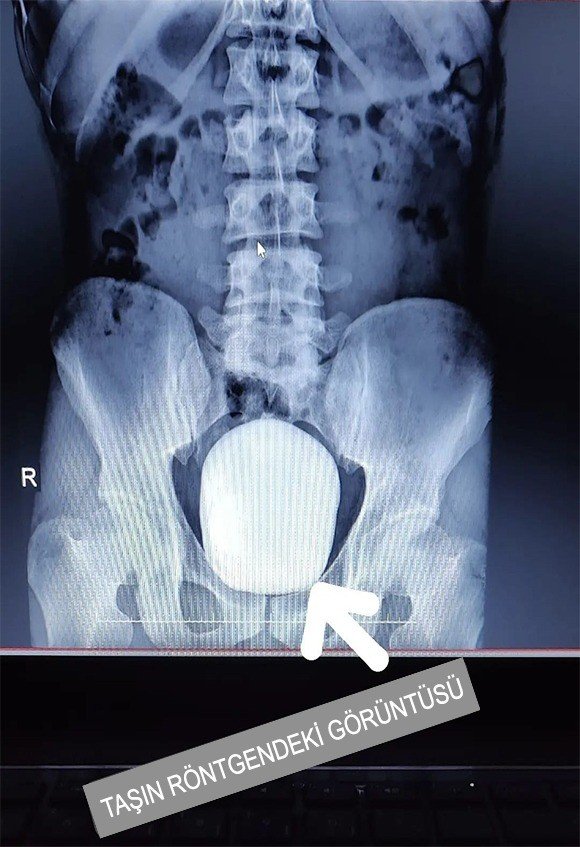

Edinilen bilgiye göre, 27 yaşındaki B.Y., isimli hasta idrar yanması şikayeti ile Karaman Eğitim ve Araştırma Hastanesine başvurdu. Çekilen röntgeninde hastanın mesanesinde 2 adet büyük çapta taş tespit edildi. Doç. Dr. Güven Erbay ve Dr. Öğretim Üyesi Ahmet Şanlı tarafından yapılan cerrahi operasyonla hastanın mesanesindeki 2 taş başarılı bir şekilde alındı.

Başarılı geçen ameliyatla ilgili konuşan Doç. Dr. Güven Erbay, "Hastamız idrar yanması şikayeti ile kliniğimize başvurdu. Yaptığımız tetkikler ve görüntülemeler sonucunda mesane içinde 15x10 santim dev boyutta bir adet ve mesane içindeki divertikül içinde de yaklaşık 4x3 santim olmak üzere toplamda iki adet taş tespit ettik. Literatürde tüm dünya genelinde kayıtlara geçen en büyük mesane taşının ağırlığı bin 900 gram olduğu bilinmektedir. Çıkarılan taşların toplam ağırlığı bin 50 gram olarak tespit edildi. Bu büyüklükteki ve ağırlıktaki dev mesane taşının Türkiye sınırları içerisinde çıkarılan en büyük mesane taşı olduğunu düşünmekteyiz" dedi.